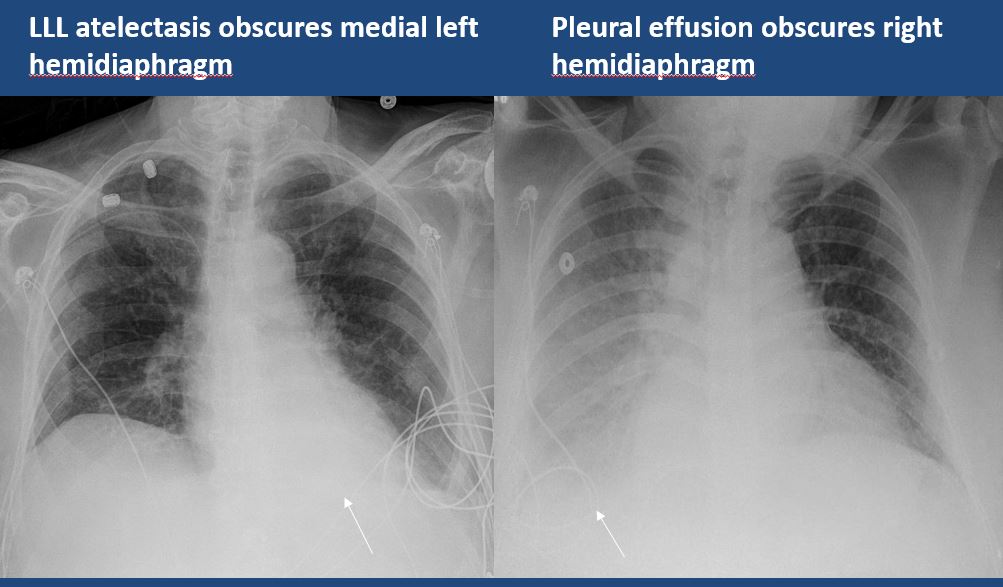

There is focal or lobar atelectasis or total collapse of the lung. [Yes/No]

There is elevation, depression, or contour abnormality of the right or left hemidiaphragm. [Yes/No]

The right or left hemidiaphragm is focally or diffusely obscured. [Yes/No]

There is a pleural effusion or blunting of the costophrenic angle. [Yes/No]